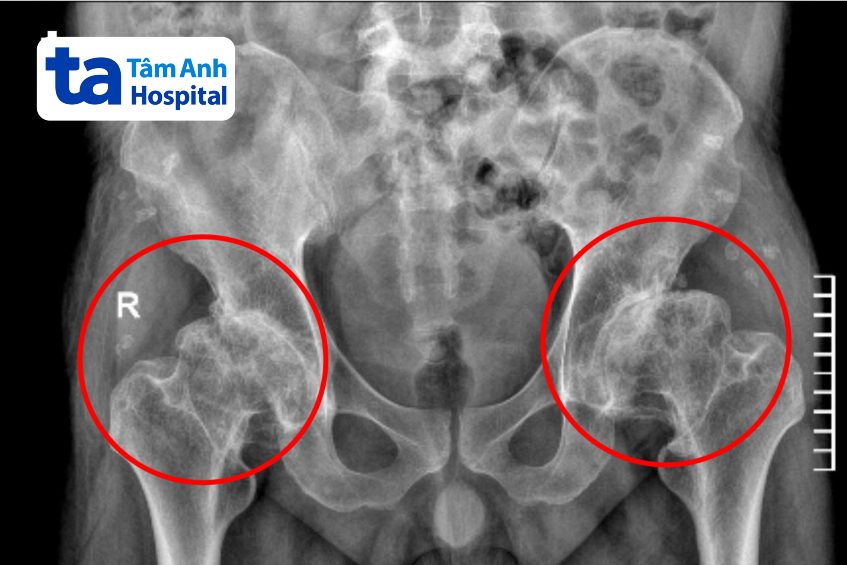

ThS.BS.CKI Đặng Khoa Học, Trưởng khoa Chấn thương Chỉnh hình Tổng quát, Bệnh viện Đa khoa Tâm Anh TP HCM, cho biết kết quả chẩn đoán cho thấy tình trạng hoại tử chỏm xương đùi của anh Điền đã phát triển đến giai đoạn cuối, chỏm xương đùi dính chặt vào ổ cối xương chậu, khiến khớp háng như đóng băng, biến dạng, gây đau đớn và không thể đi lại bình thường. Để phục hồi lại dáng đi và vận động, người bệnh được chỉ định phẫu thuật thay hai khớp háng với mức độ phức tạp.